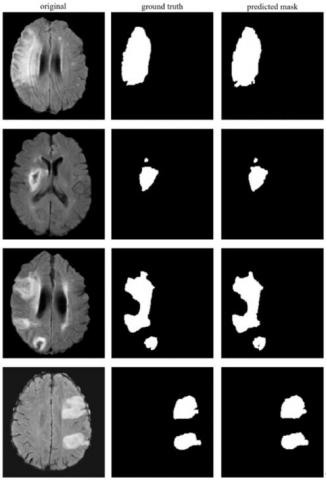

In experimental studies using the stroke dataset with the U-Net technique, 0.92 segmentation scores on pixel basis according to the DSC metric, and 0.89, 0.95 and 0.92 scores according to the PRC, RC and F1 metrics were achieved, respectively. The results from some of the ISLES 2015 MR images for stroke detection are shown in Figure 9. Here, the original MR image, ground truth masks of the stroke lesion area marked by the expert, and semantic segmentation masking of the lesion areas detected with U-Net are given for four different MR images. As a result of the experimental studies performed by the Mask R-CNN using the stroke dataset, 0.93 DSC score was achieved on pixel basis. In addition, as a result of the experiments, 0.97 PRC, 0.98, RC and 0.98 F1 scores were achieved.

Figure 9. U-Net segmentation results in ISLES 2015 dataset for some MR images